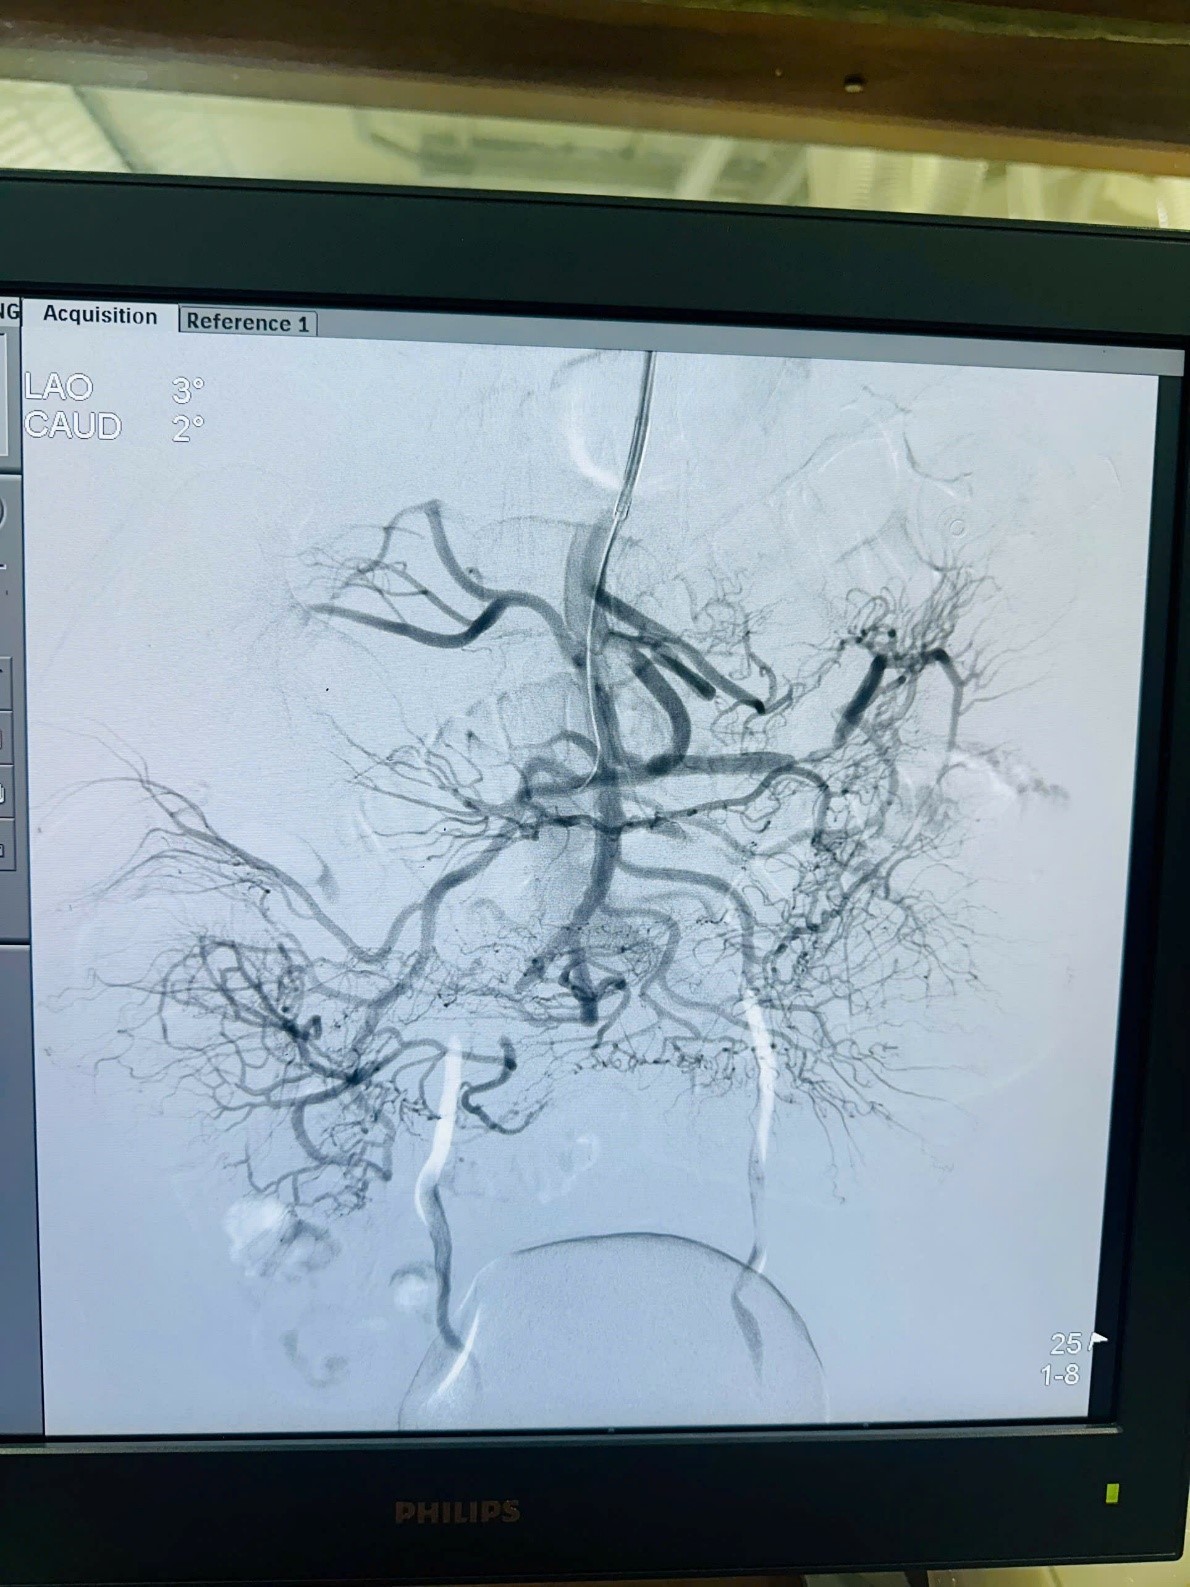

Hình 2: Động mạch mạc treo tràng trên được can thiệp tái thông